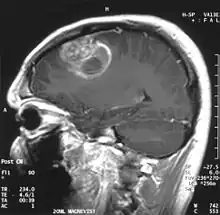

Le premier produit de contraste mis au point pour l'IRM est le gadolinium (Gd). En raison de sa toxicité, il faut l’emballer (le chélater) dans une molécule de DTPA. On a ainsi obtenu en 1984 le Gd-DTPA[81], qui avait le potentiel pour obtenir des IRM renforcés pour le diagnostic de lésions locales de la barrière hémato-encéphalique[82]. La molécule de Gd-DTPA est très polaire, et par conséquent bien trop hydrophile pour traverser une barrière hémato-encéphalique saine. Les modifications des jonctions serrées, comme celles qui peuvent par exemple être provoquées par un glioblastome, permettent le transport paracellulaire de ce produit de contraste dans le tissu cérébral. Là, il renforce le contraste, par interaction avec les protons de l'eau environnante, et rend visibles les défauts de la barrière hémato-encéphalique. Comme ce sont les vaisseaux responsables de l'alimentation de la tumeur qui sont touchés, dans son voisinage immédiat, on peut en apprécier l'extension.